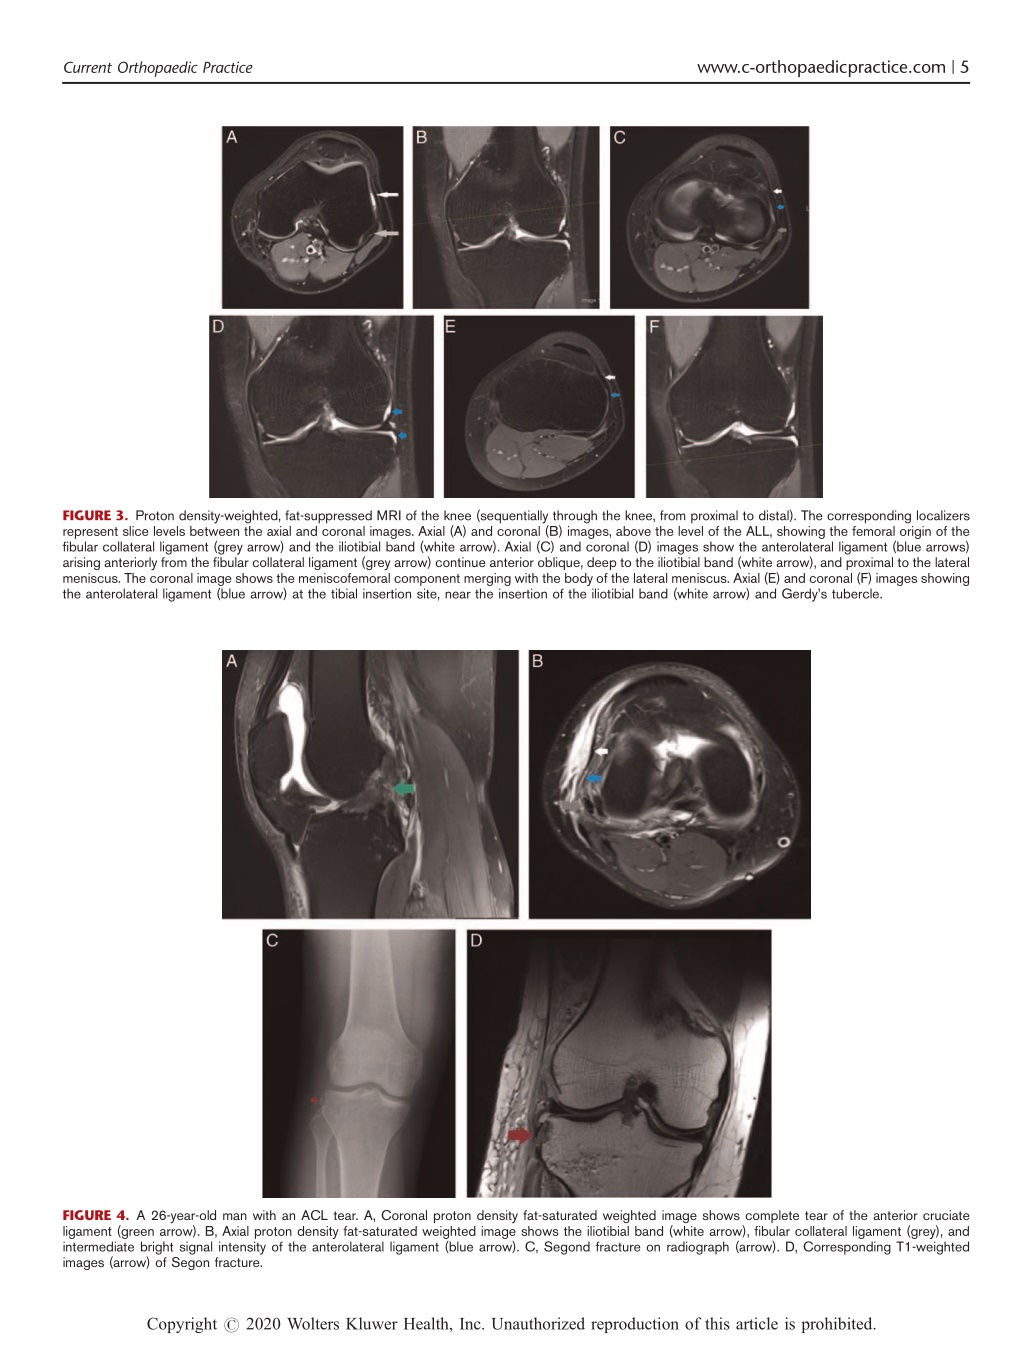

5. www.c-orthopaedicpractice.com | 5 Current Orthopaedic Practice FIGURE 3. Proton density-weighted, fat-suppressed MRI of the knee (sequentially through the knee, from proximal to distal). The corresponding localizers represent slice levels between the axial and coronal images. Axial (A) and coronal (B) images, above the level of the ALL, showing the femoral origin of the fibular collateral ligament (grey arrow) and the iliotibial band (white arrow). Axial (C) and coronal (D) images show the anterolateral ligament (blue arrows) arising anteriorly from the fibular collateral ligament (grey arrow) continue anterior oblique, deep to the iliotibial band (white arrow), and proximal to the lateral meniscus. The coronal image shows the meniscofemoral component merging with the body of the lateral meniscus. Axial (E) and coronal (F) images showing the anterolateral ligament (blue arrow) at the tibial insertion site, near the insertion of the iliotibial band (white arrow) and Gerdy’s tubercle. FIGURE 4. A 26-year-old man with an ACL tear. A, Coronal proton density fat-saturated weighted image shows complete tear of the anterior cruciate ligament (green arrow). B, Axial proton density fat-saturated weighted image shows the iliotibial band (white arrow), fibular collateral ligament (grey), and intermediate bright signal intensity of the anterolateral ligament (blue arrow). C, Segond fracture on radiograph (arrow). D, Corresponding T1-weighted images (arrow) of Segon fracture. Copyright r 2020 Wolters Kluwer Health, Inc. Unauthorized reproduction of this article is prohibited.